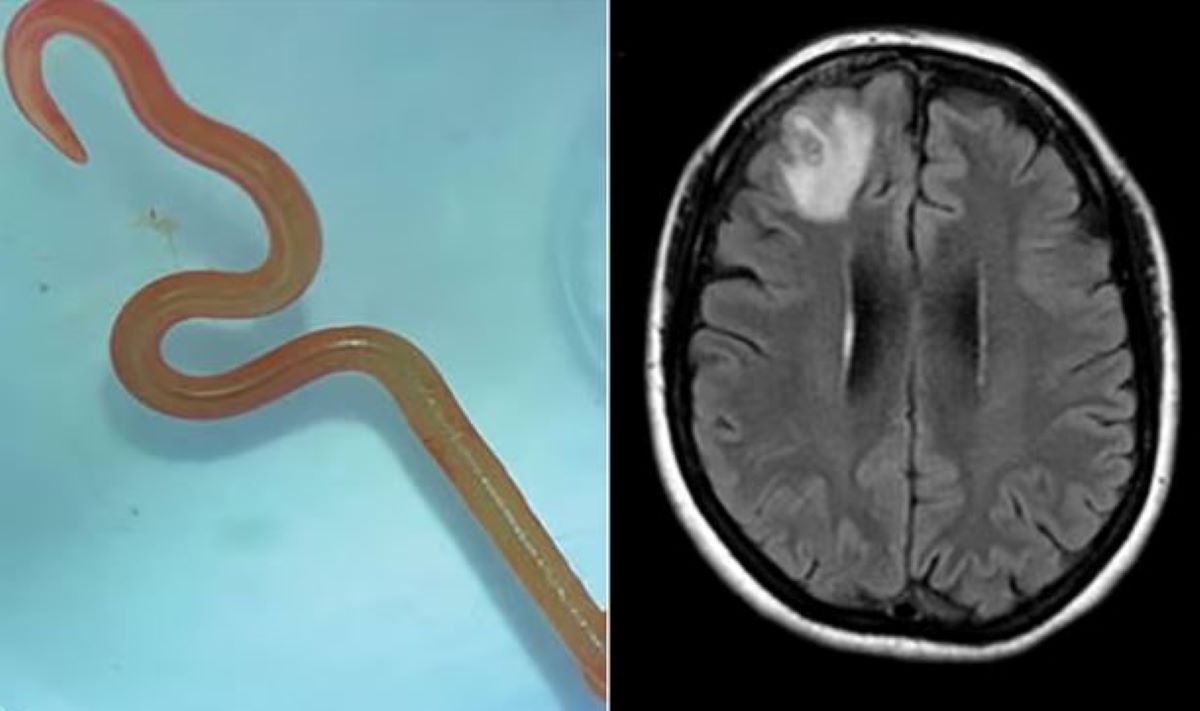

Σοκαρισμένοι ήταν οι γιατροί μίας κλινικής στην Αυστραλία όταν αφαίρεσαν από τον εγκέφαλο μίας 64χρονης γυναίκας ένα ζωντανό σκουλήκι μήκους 8 εκατοστών.

Η περιπέτεια υγείας της γυναίκας ξεκίνησε στα τέλη του 2021 όταν επί 3 εβδομάδες εισήχθη στο νοσοκομείο με πυρετό, πόνο στην κοιλιά, διάρροια, βήχα και νυχτερινές εφιδρώσεις. Έως το 2022 η γυναίκα παραπονέθηκε ότι ξεχνούσε συχνά και είχε συμπτώματα κατάθλιψης. Τότε οι γιατροί την υπέβαλαν σε μαγνητική τομογραφία και διαπίστωσαν ανωμαλίες στον εγκέφαλο της. Αποφάσισαν να την εγχειρίσουν και έμειναν άφωνοι όταν εντόπισαν το σκουλήκι.

Οι γιατροί του νοσοκομείου προσπάθησαν να ταυτοποιήσουν το σκουλήκι προκειμένου να βοηθήσουν την ανάρρωση της 64χρονης. Έτσι το έστειλαν σε εξειδικευμένο εργαστήριο για παράσιτα. Οι επιστήμονες του εργαστηρίου τους ενημέρωσαν ότι το σκουλήκι είναι το Ophidascaris robertsi.

Το συγκεκριμένο παράσιτο βρίσκεται συνήθως σε πύθωνες αλλά αυτή είναι η πρώτη περίπτωση που εντοπίστηκε σε ανθρώπινο οργανισμό. Πράγματι η 64χρονη διέμενε κοντά σε μία λίμνη, που είναι γεμάτη με πύθωνες. Αν και δεν είχε κάποια επαφή με φίδι η 64χρονη είπε στους γιατρούς της ότι μάζευε και μαγείρευε χόρτα από την λίμνη.

Τώρα οι γιατροί και οι επιστήμονες που την παρακολουθούν υποθέτουν ότι το παράσιτο μεταφέρθηκε στα χόρτα από κάποιον πύθωνα. Στη συνέχεια μόλυνε την 64χρονη είτε επειδή ακούμπησε τα χόρτα είτε επειδή τα έφαγε. Η 64χρονη αναρρώνει και η κατάσταση της υγείας της κρίνεται καλή, ενώ παραμένει υπό παρακολούθηση.